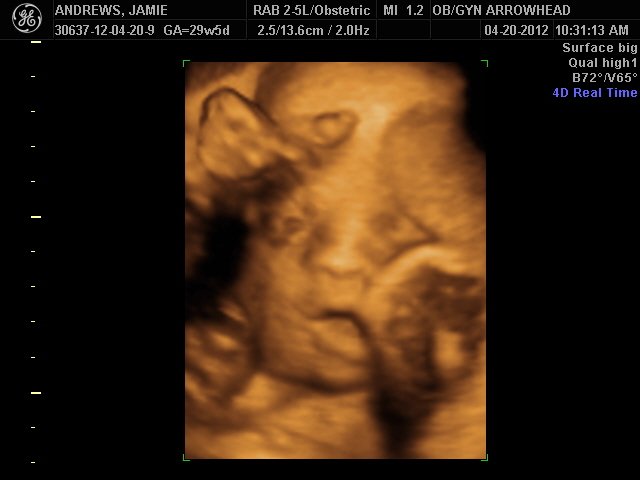

We offer complimentary 3D/4D Ultrasounds to all our OB patients around 30 weeks! The following photos are some examples of our work, shown with permission from our patients.